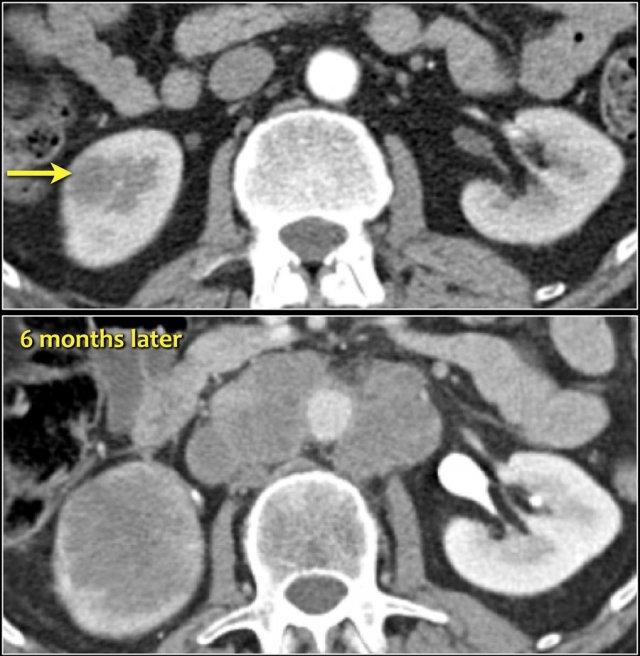

Tổn thương xâm lấn ở cực dưới thận phải, phát triển đáng kể sau sáu tháng, kèm theo hạch bạch huyết lan rộng. Đây được xác định là di căn của ung thư phổi.

Các khối u ác tính nguyên phát thường di căn đến thận nhất bao gồm ung thư phổi, ung thư vú, các khối u đường tiêu hóa và u hắc tố (melanoma).

Di căn thận thường xuất hiện muộn trong tiến trình của một bệnh ác tính đã biết, như một phần của bệnh lan rộng toàn thân.

Trong một số ít trường hợp, di căn thận có thể biểu hiện dưới dạng một tổn thương đơn độc và khó phân biệt với ung thư biểu mô tế bào thận.

Sinh thiết qua da có thể được thực hiện để giải quyết vấn đề này.

Di căn thận thường có kích thước nhỏ, đa ổ và hai bên, với hình thái phát triển xâm lấn.